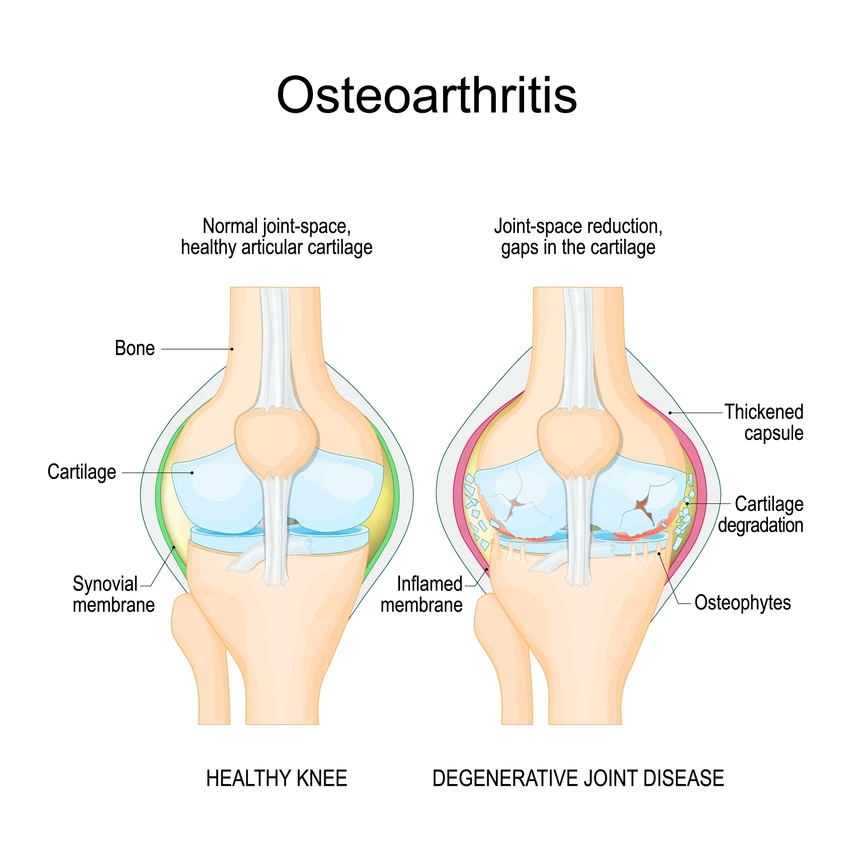

Cartilage - Cartilage is a flexible, rubbery connective tissue that provides cushioning and support at joints. It reduces friction between bones and absorbs shock.

Osteoarthritis (OA)

A degenerative joint disease characterized by the breakdown of cartilage and the underlying bone. It can be caused by aging, joint injury, obesity, and genetic factors. Symptoms to watch for include joint pain, stiffness, swelling, and decreased range of motion.